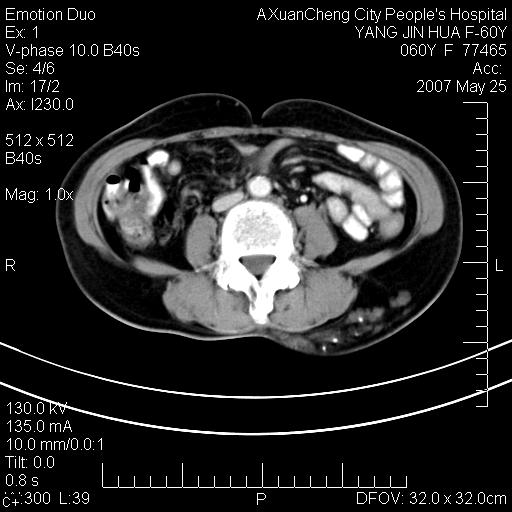

发现左侧腰背部包块40余年,逐渐长大,质软,局部表面可见扩张的血管影

左背部皮下良性肿瘤,密度不均,边界不清,内有脂肪、钙化,增强扫描无明显强化,血管平滑肌脂肪瘤?进一步诊断有困难,建议穿刺活检。

左侧背部皮下混杂密度肿块,结构较疏松,边缘欠光整,内有多发斑点状钙化,考虑:皮下血管瘤。

这个病理增强扫描之前,我们是考虑是血管瘤,可是现在增强后一点强化都没有,还能考虑是血管瘤吗